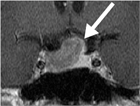

1. 先端巨大症は成長ホルモン(GH)が慢性過剰に分泌されることにより引き起こされる。この過剰分泌のほとんどは良性のGH産生下垂体腫瘍が原因である。

1. 症状には、特異的な所見である手足の容積の増大、先端巨大症様顔貌(眉弓部の膨隆、鼻・口唇の肥大、下顎の突出など)、巨大舌と発汗過多、頭痛、視力、視野障害、女性における月経異常、睡眠時無呼吸症候群、耐糖能異常、高血圧、不正咬合、変形性関節症、手根管症候群、頭蓋骨および手足の単純X線の異常などがある。